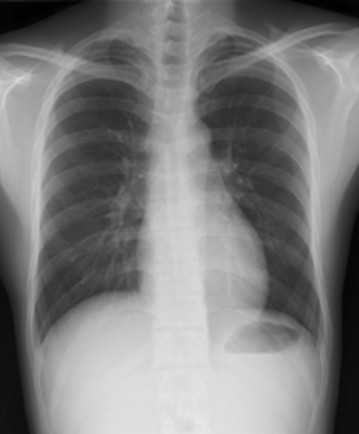

X線撮影室

胸部・腹部および全身骨部のX線撮影を行っています。

撮影部位によって着替えをお願いしています。

湿布・カイロ・アクセサリー等は外していただく場合があります。